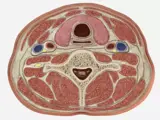

With SIMTICS students can learn and practice a wide range of ultrasound procedures and protocols, anytime and anywhere. No downloads and no special equipment required. Choose from 24+ hours of content featuring a range of ultrasound procedures, including general, cardiac and vascular assessments and several that students may not be allowed to practice during externships. As well as interactive simulations, each module includes a demonstration video, explanatory text with key terms and illustrations, an applied anatomy section with 2D and 3D images, and at least one quiz to test your theory knowledge.